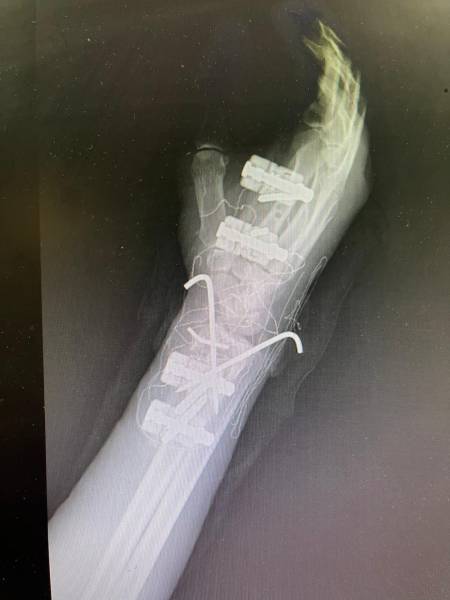

- إجراء عمليات جراحية معقدة و دقيقة في مجال العظام و المفاصل و الكسور و الإصابات ، رغم الضغط الكبير على المستشفى و أعداد المراجعين الكبيرة.

- تطبيق تقنيات جراحية حديثة و متقدمة، و ذلك في ظل التحديات التي يواجهها الفريق بسبب أعداد المرضى و المراجعين الكبيرة.